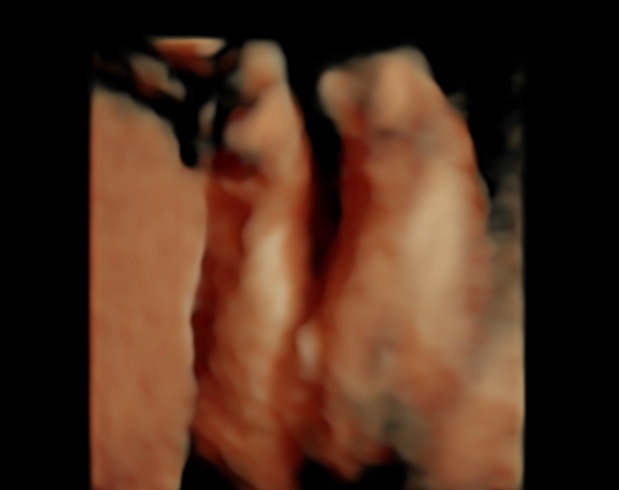

Can anybody see the gender? The legs are close together so it's hard to see. The person who performed the ultrasound thought boy but I'm not sure!

Thank you in advance :)

If the sonographer was a professional and they thought boy, I'd be inclined to believe them x

Thank you for your answer. That's what I thought too, the first time. I've had 3 ultrasounds. The first one said boy, the second said girl and this one said boy, that's why I don't really trust them :)

Boy lean